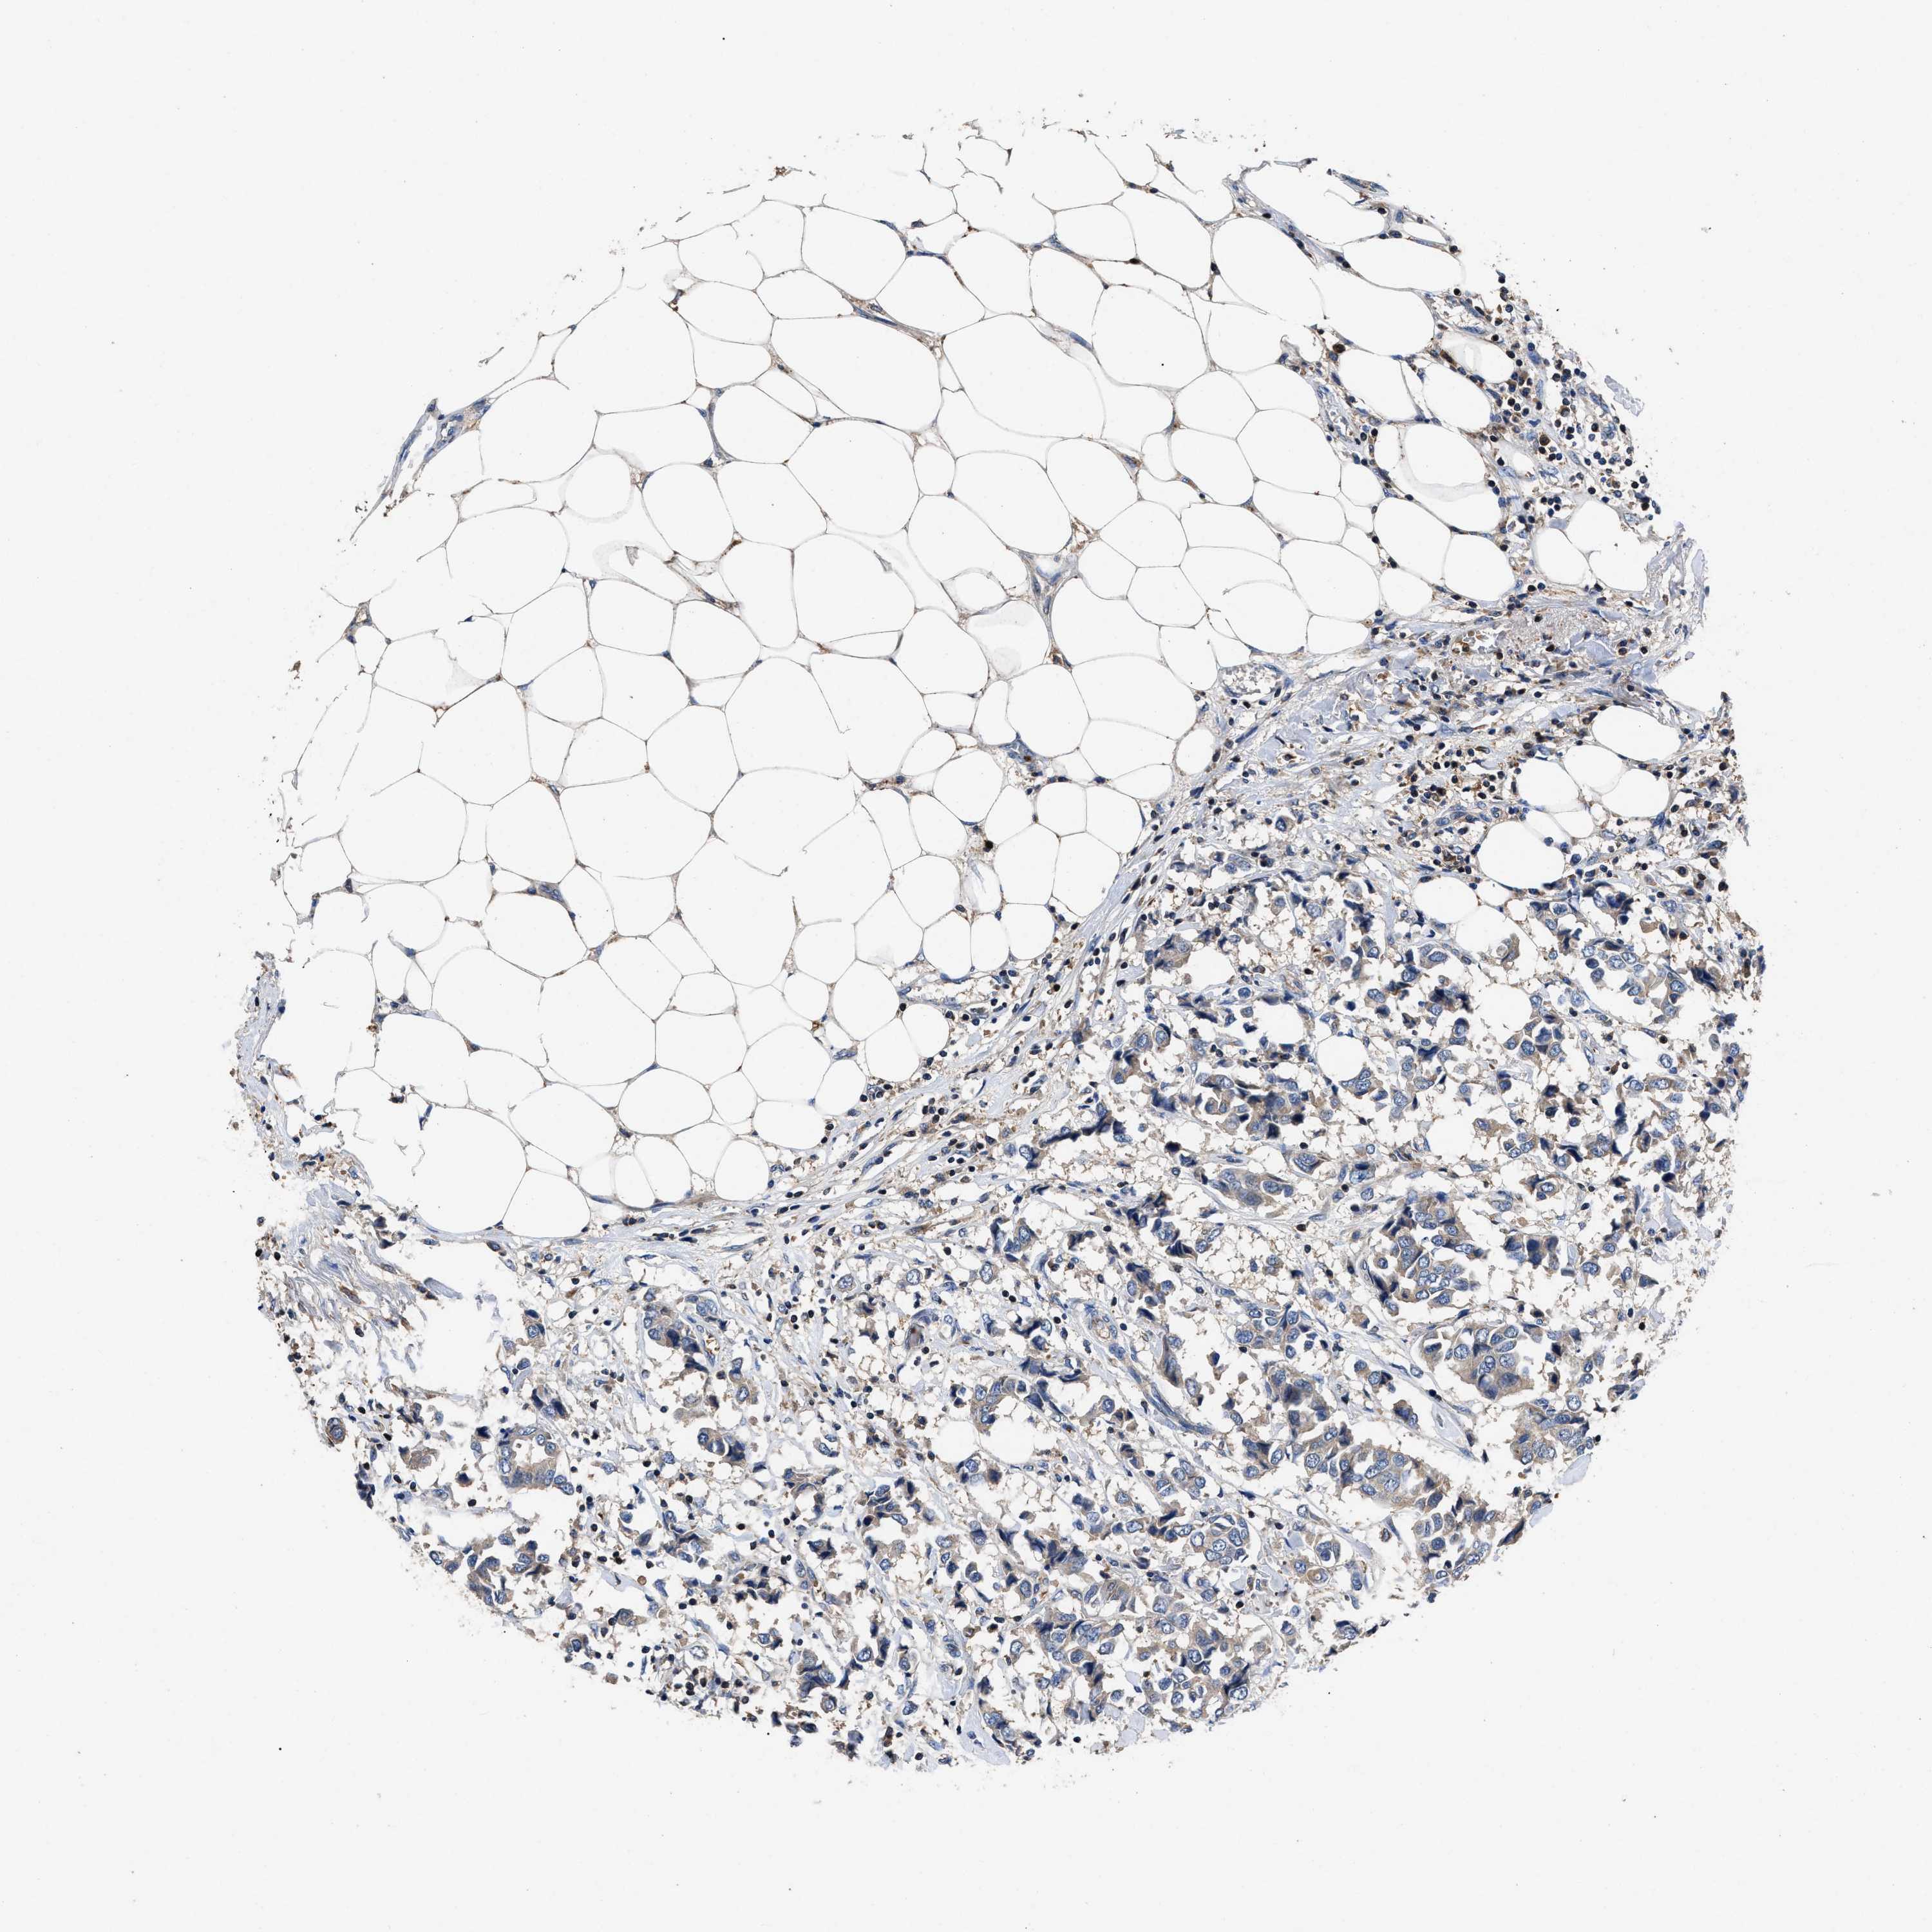

CANCER BREAST CANCER Show tissue menu

BRCA TCGA BRCA VALIDATION PROTEIN EXPRESSION

Breast cancer

Human cancer